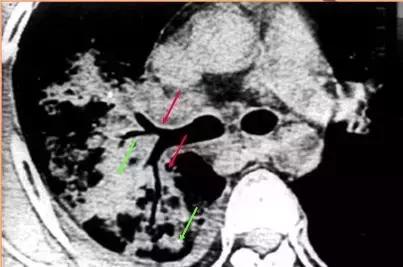

CT征象九:空气新月征

肺内空洞或空腔内的球形病灶与洞壁之间形成的新月形透亮影称为“空气新月征”。

空气新月征曾认为是曲霉菌球的特异征象,特点是随着体位的变动,空洞或空腔内的霉菌球可移动,但始终位于近地位。也可见于其他疾病(其内球形病灶可能不移动)

仰卧与俯卧位CT扫描,霉菌球始终处于近地位,空气新月征位于上方

同影异病:案例

“空气新月征”也可见于肺结核病例,常伴有钙化,多不随体位而变动